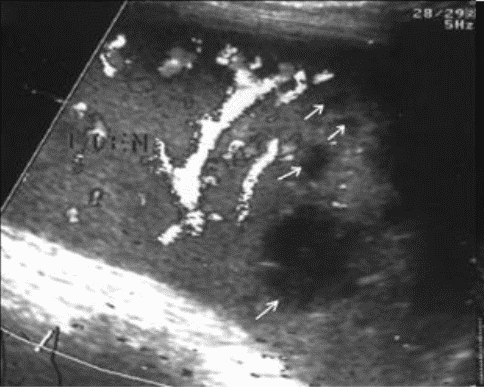

Чрескапсульные разрывы селезенки манифестируют нарушением непрерывности контура органа и визуализацией внутриорганных линий разрыва (рис. 7). Последние представляют собой гипоэхогенную или эхонегативную, в зависимости от времени, прошедшего после травмы, зону линейной или "ветвистой" формы с неровными и нечеткими контурами. Важно отметить, что прямые эхографические признаки, будучи патогномоничными для данного вида повреждений, не имеют облигатный характер. В частности, нарушение непрерывности контура селезенки наблюдается только у 25,4% больных, а линия внутриорганного разрыва визуализируется в 60,3% случаев. При этом возможность выявления указанных признаков в ранние сроки весьма проблематична и становится реальной только через 16 - 24 часа после травмы.

Рис. 7. Эхограмма чрескапсульного разрыва селезенки. Нарушение непрерывности контура указано стрелкой.